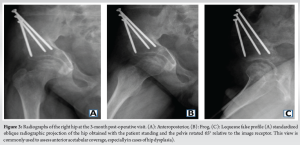

After obtaining parental consent, a right-sided triple pelvic osteotomy was performed 6 months after initial evaluation. The right hip had a full, painless passive range of motion 3 months post-operatively. Radiographs showed a well-healing osteotomy with abundant callus (Fig. 3). At 1-year post-operative, the patient remained pain-free on the right, with radiographs demonstrating a healed osteotomy and re-ossification of the femoral head. With improved sphericity and acetabular coverage, the femoroacetabular relationship is more adequate, and his waddle gait almost disappeared completely. However, he continued to experience activity-related pain in the left hip, particularly with deep flexion. At that time, a left-sided triple pelvic osteotomy was scheduled along with the removal of hardware from the right hip.